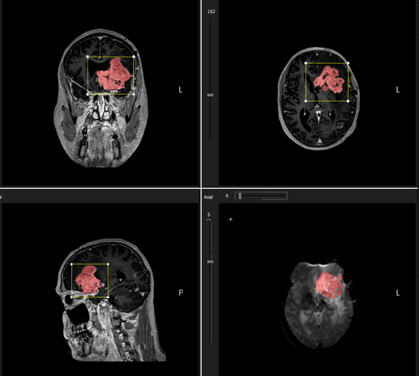

Figure 2: Sample result of initial 3D seed

growing from placing a single seed point within tumor region. The VOI sets

the limitation of the seed growing extension